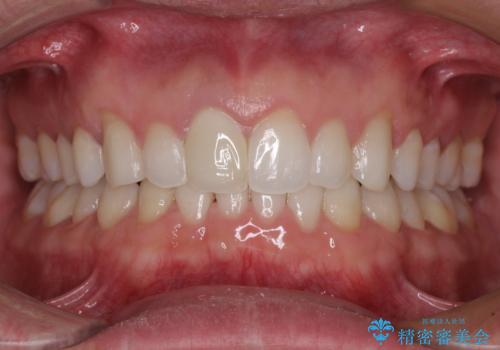

出っ歯を改善した後に真っ白な歯に 矯正歯科治療と審美歯科治療